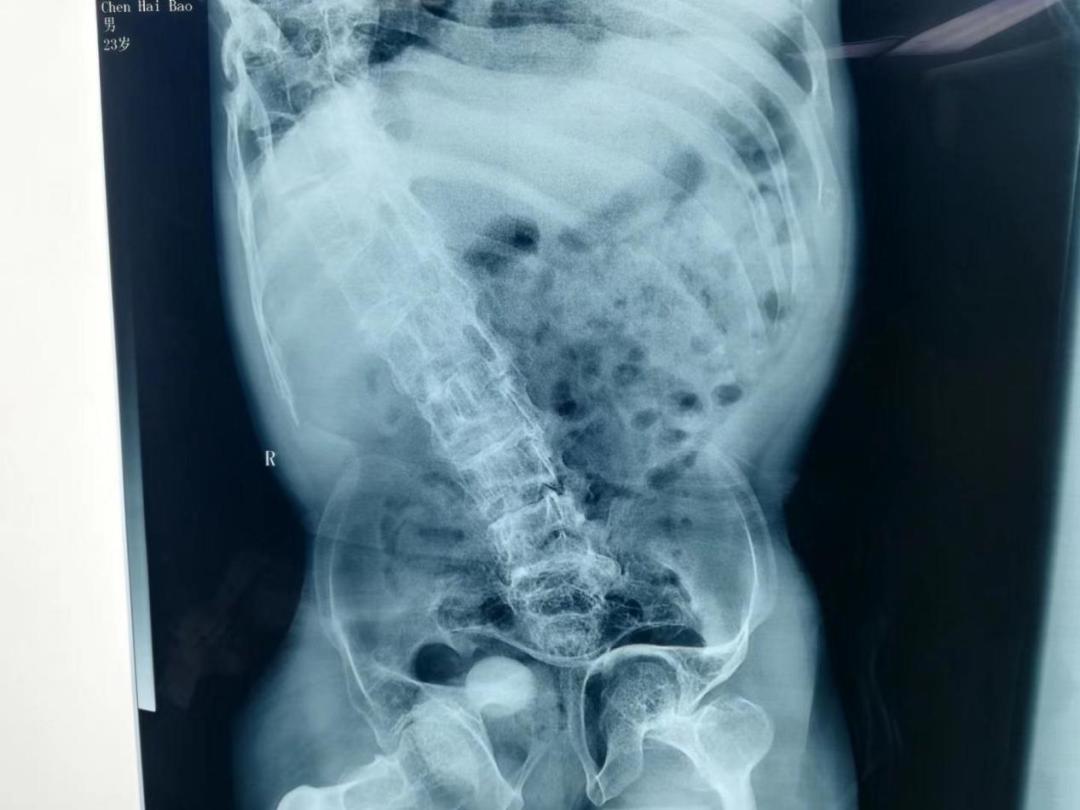

一名23岁“玻璃人”患者来到锦州医科大学附属第一医院。稍微蹦跳就会发生大腿骨折的他患有肾结石。由于脆骨症自幼多发骨折导致他的骨骼严重畸形,患肾已经部分上移至胸腔内……情况非常复杂,治疗难度非常大。泌尿结石病区张大田主任、田洪阳医生团队经过反复术前讨论,结合患者的特殊情况,决定为患者实施经皮肾镜碎石取石术,术中选取穿刺禁区的第10肋间作为穿刺点,在与麻醉科王昊主任、任宏伟医生以及手术室护士的共同努力下,仅一个小时就成功完成了手术。